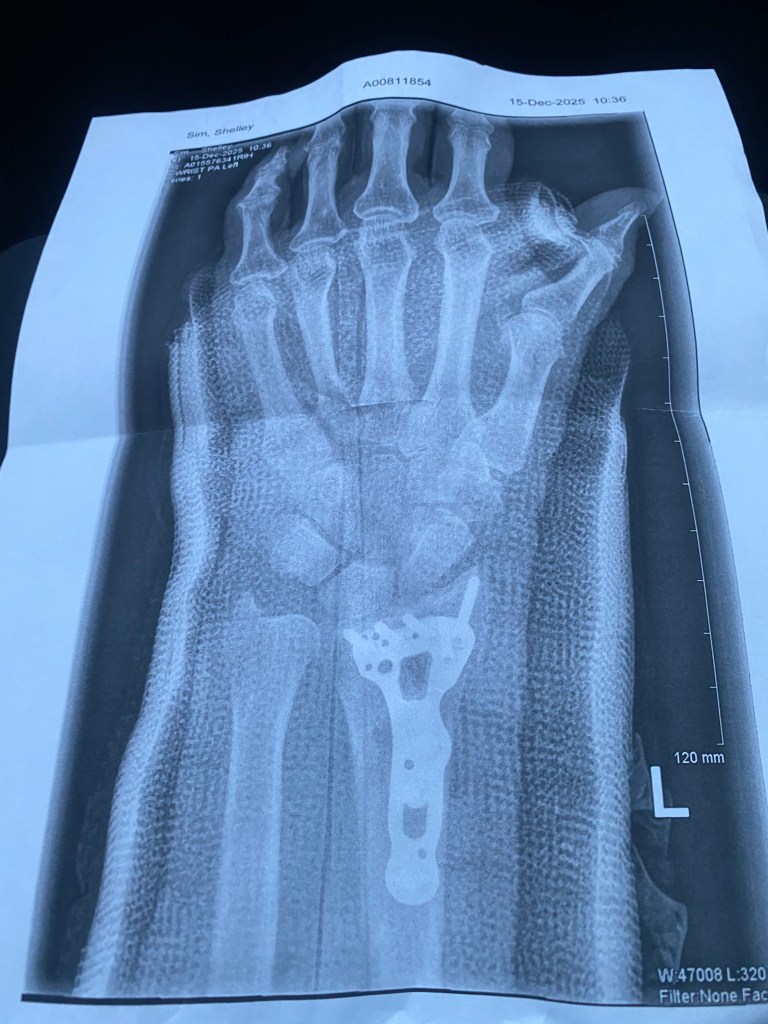

I remain eternally grateful that our little town has a hospital and a wonderful medical team. The xray confirmed that the wrist had shattered rather nicely and because it was pretty bad, they had to do a closed reduction. This sounded very civilized or maybe anything sounded good when under the influence of fantastic drugs.

A closed reduction is painful. They have to try and put the bones back into some sort of alignment which involved separating the bones and trying to put them back so they looked kind of straight. More drugs, a light anesthesia and at least the bones were stretched and kind of back together.

Fast forward to the next day when my daughter Megan drove into the “big” city for an ortho consult. It was really incredible. Almost abandoned in the woods and less than 18 hours later I had surgery and was sent home with a plate and 9 screws in my arm and bundled up in a cast with strict orders not to pick up anything; not even a teacup for the next six weeks.